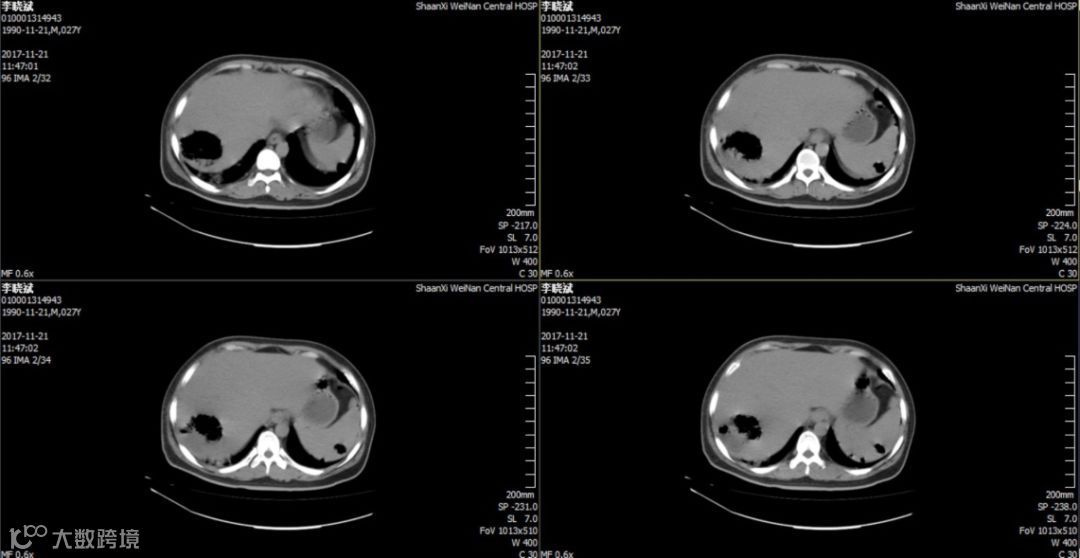

入院后第2天胸腹部CT:双肺所见,考虑特殊菌感染可能,腹腔少许游离气体,肝右叶混杂密度包块。

血培养:肺炎克雷伯杆菌亚型,常用药物均敏感。

2018.11.25复查CT:双肺炎症,考虑特殊细菌感染可能,双侧胸膜腔少量积液,心包少量积液,腹腔少量积液,少许游离气体,部分包裹,肝右叶、脾实质混杂密度包块,脓肿并气体。因经济原因换用头孢曲松 2.0 g,QD,ivgtt。12月8日再次发热,12月12日肝脏穿刺引流后体温逐渐正常,CT提示病灶逐渐吸收。